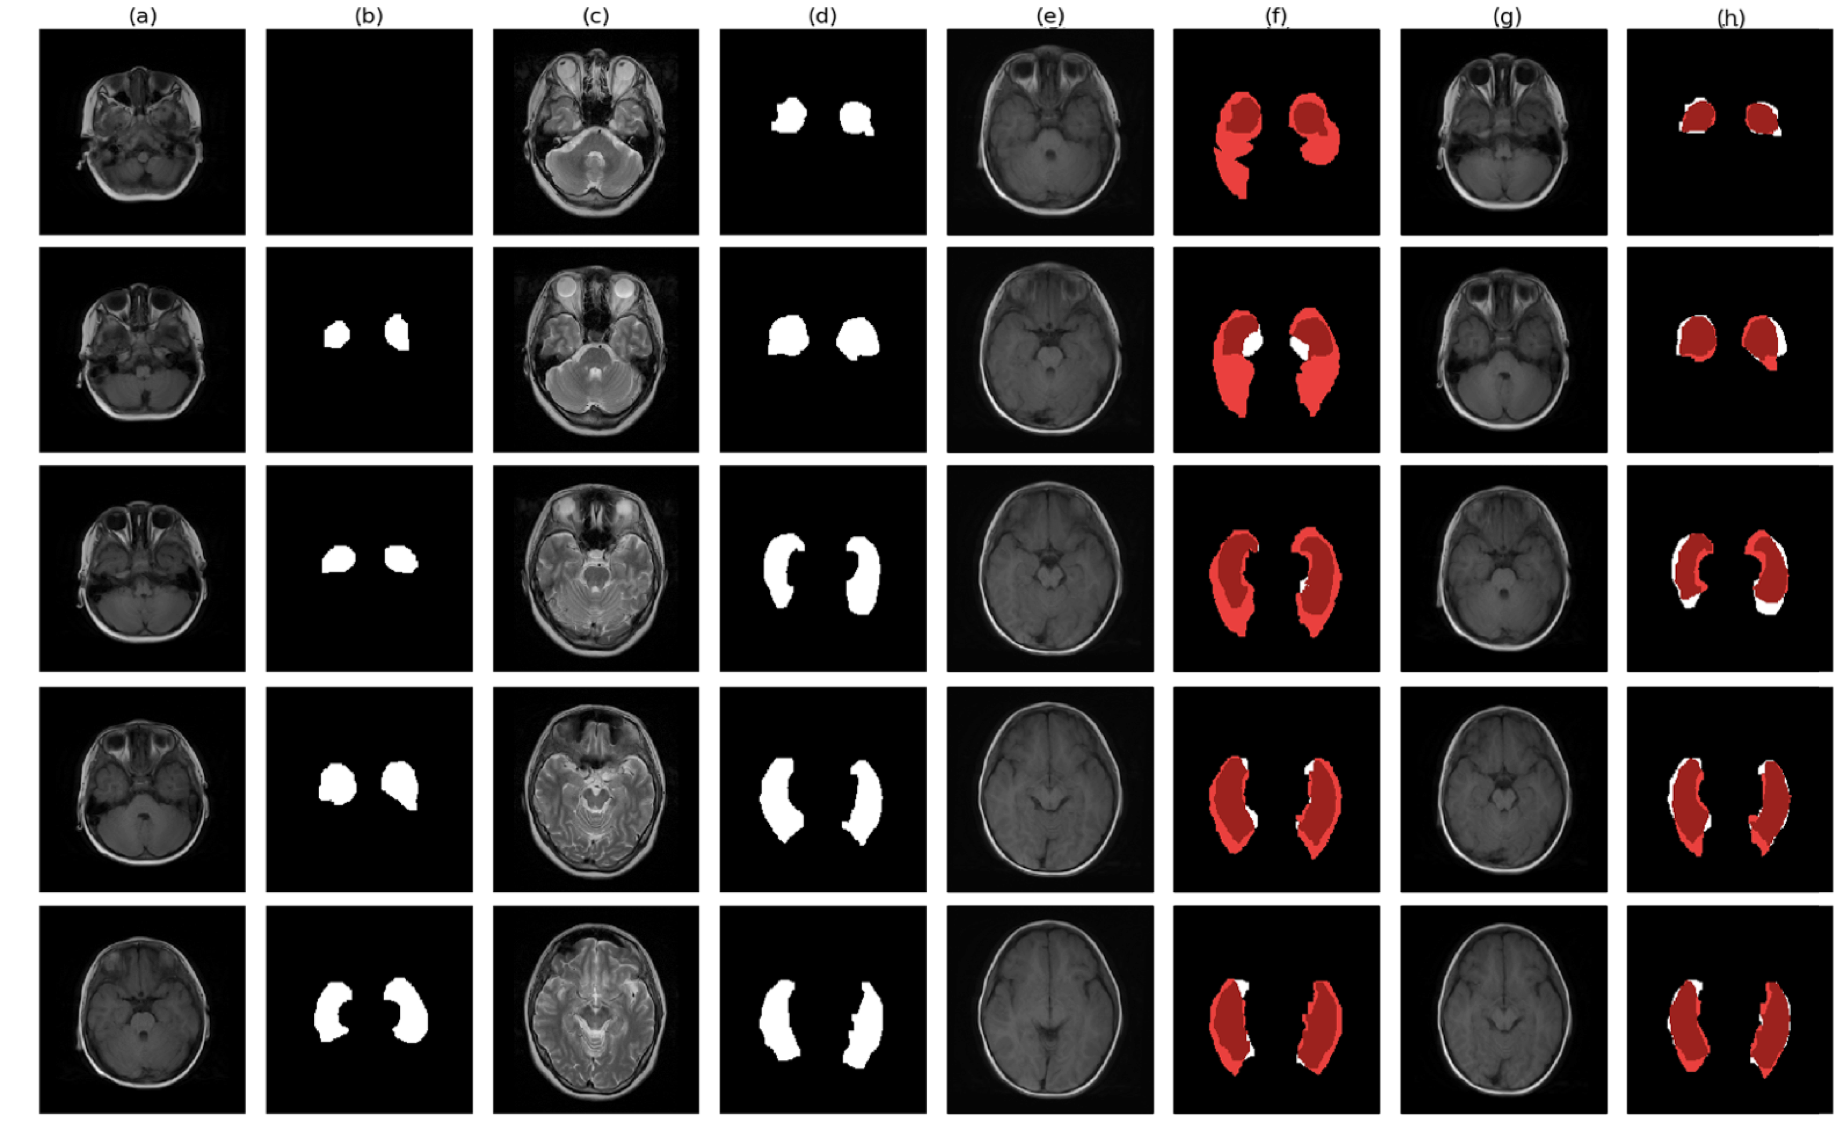

The estimated transformation parameters are then fed into the resampler to wrap the corresponding segmentation masks. We firstly evaluate the metrics on the segmentation mask of one particular brain part, which is the temporal lobe and the performance of our neural registration models and the conventional method are shown in Table 1. Our proposed models have relatively constant execution speed and are 100x faster than the conventional method. At the same time, they still achieve better overall registration performance for this region. Fig. 4 illustrates an example of the registration results from experiment .

Next, we evaluate the performance of the methods on ten out of the eighteen brain regions which are labelled. We note that in some methods, only affine transformation is involved and hence, not all of the brain parts will be registered perfectly. The registration performance could vary across different brain regions and the results are shown in Fig. 5 and Table 2.